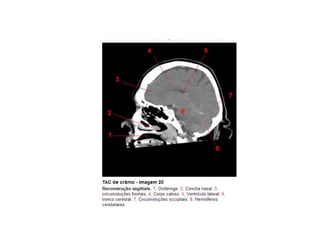

Anatomia E Protocolo Tomografia Computadorizada de Crânio PPT